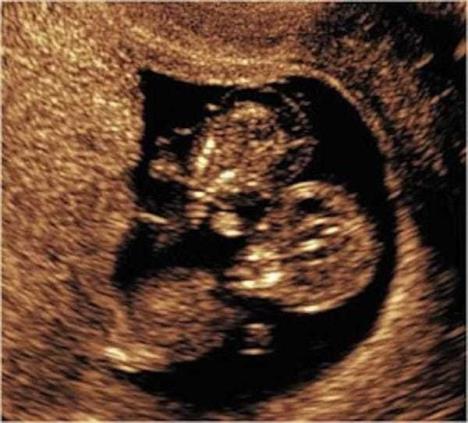

Kada je otkrila da je nosi blizance, Kejt su saopštili doktori da su njene bebe i stresnoj situaciji koja se zove, monoamniotik ili "MoMo", i da verovatno neće preživeti.

MoMo je retko stanje gde blizanci u majčinoj utrobi nemaju membranu koja ih odvaja. Njihove pupčane vrpce su se zamotale oko njih dok su rasli. Lekari su ovim bebama dali šanse 50-70% za preživljavanje.

Njihove spojene pupčane vrpce su ispitivane, a lekari su zapanjeni kako su bebe preživele trudnoću. Isprepletanost je opasnija nego što se ranije mislilo i čak je na jednom mestu postojao čvor.